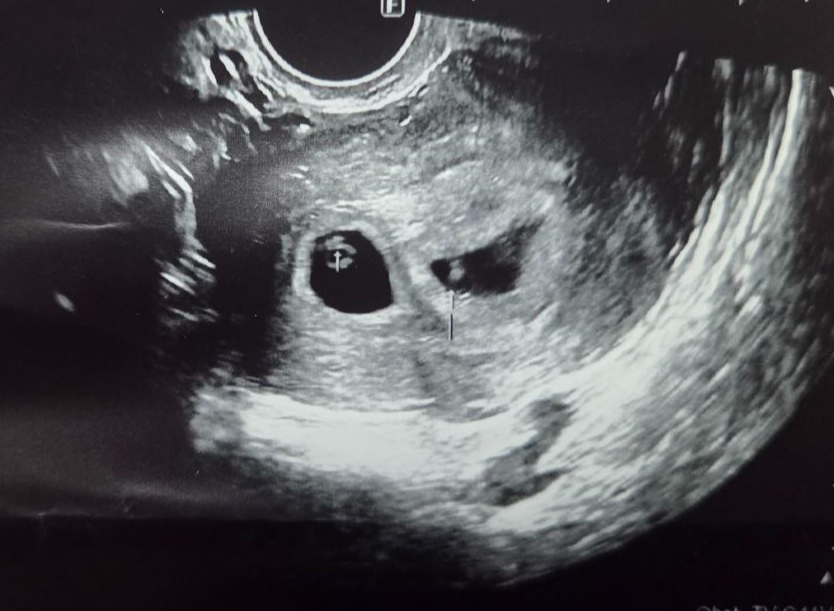

2025년 5월 30일, 임신 6주 0일에 첫 초음파를 통해 다태아 임신임을 확인받고 공식 임신확인서를 발급받았어요. 저는 귀여운 애플이들(태명)을 품은 쌍둥이 엄마랍니다~:) 지난 5주차보다 훨씬 또렷해진 아이들의 모습을 보니 기특하면서도 아직은 현실감이 덜 느껴지네요.